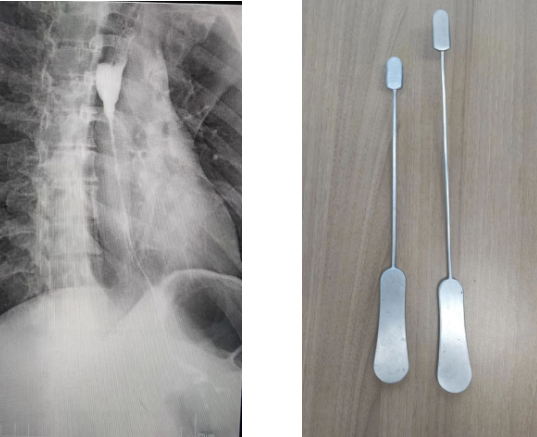

為了建立胸骨后的人工隧道,李小飛教授還自制了一把特殊的彎鉗,用于做胸骨后隧道便于將結(jié)腸順利從腹腔經(jīng)過胸骨后隧道提至頸部。